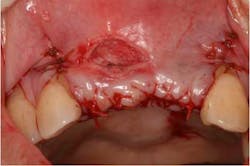

A 43-year-old female with a noncontributory medical history taking no medication and having no known food/drug allergies presented to my general dental office with a chief complaint of having “loose teeth with an underbite.” Clinically, she had generalized, moderate, chronic periodontal disease and was missing teeth Nos. 8 through 10. She had a Class III malocclusion with pathologic flaring of her remaining anterior teeth. She had both vertical and horizontal tissue loss in the No. 8 through 10 region. The patient wore a transitional partial denture to replace the anterior missing teeth that was placed in edge-to-edge occlusion by her previous dentist. (Fig. 1) She did not like having a removable prosthetic and desired a fixed option in the form of implants to replace her missing teeth. I sent her to the periodontist for a periodontal consult for her remaining dentition and dental implants to replace her missing front teeth.

Fig. 2